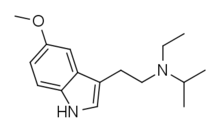

| EiPT | artificial | H | CH2CH3 | CH(CH3)2 | N-Ethyl-N-isopropyltryptamine | 848130-11-0 |